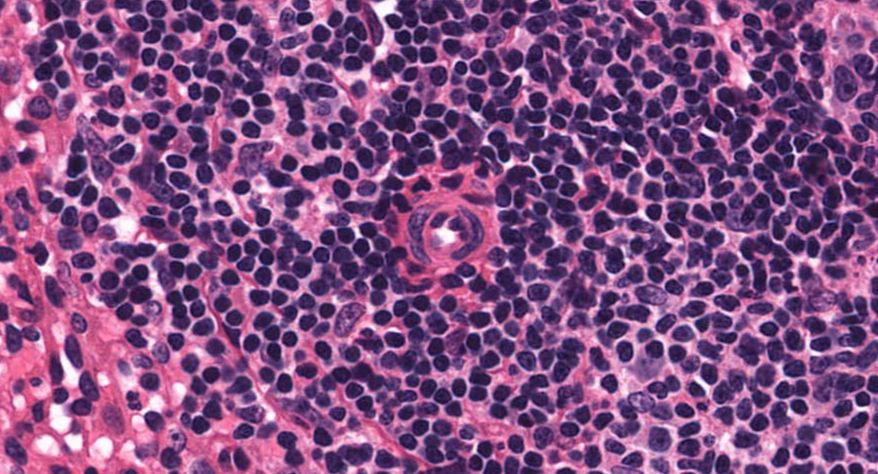

低倍镜:胸腺表面包有薄层结缔组织构成的被膜,结缔组织深入实质,将胸腺分成许多不完整的小叶。每个小叶分为周围的皮质和中央的髓质两部分。皮质中胸腺细胞排列密集,故染色深;髓质中胸腺细胞较少,胸腺上皮细胞多,故染色浅,其中可见染成红色的圆形小体-胸腺小体。高倍镜:胸腺小体大小不等,由几层至十几层扁平的胸腺上皮细胞呈同心圆状排列而成,其外周的细胞较幼稚,细胞核明显;小体中央部分的上皮细胞已退化,细胞核消失,胞质呈均质状,染成红色。

7.胸腺小体1